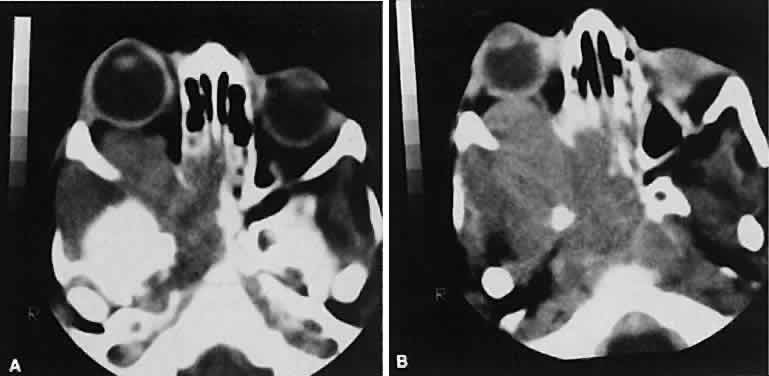

Lacrimal fossa lesions deserve separate consideration and do not fit any other convenient classification scheme. The lacrimal gland is a substrate for various tumors both benign and malignant. Benign lesions are typified by the pleomorphic adenoma (benign mixed tumor). The clinical profile of painless progressive proptosis is matched with a CT picture that shows an enlarged, sometimes nodular, well-delineated lacrimal gland (Fig. 16). Bone windows may show pressure expansion and thinning of the bone in the lacrimal fossa. Intralesional calcium61 or intralesional hemorrhage62 also may be present.

Fig. 16. Benign mixed tumor of the lacrimal gland. Axial (A) and coronal (B) views show a well-demarcated hyperdense mass that expands the fossa of the lacrimal gland by pressure effects rather than erosion. Suggestion of mixed density is apparent on the axial view, and globe displacement is evident on the coronal view.

Malignant lesions of the lacrimal gland, conversely, often appear invasive, with bone destruction evident on the CT scan (Fig. 17). Intralesional calcium may be present.63,64 The use of contrast material facilitates detection of lesions that extend beyond the confines of the orbit.

Fig. 17. Adenocarcinoma of the lacrimal gland. A. Unenhanced axial view shows the speckled calcification of a lacrimal gland tumor. B. Contrast-enhanced view at about the same level shows intense enhancement and vascularity. In axial views at a higher level, an unenhanced scan (C) is unremarkable, although a contrast-enhanced view (D) at the same level highlights intracranial extension (arrows). E. Reconstructed coronal view has bone destruction with extension into the intracranial and temporalis fossae.